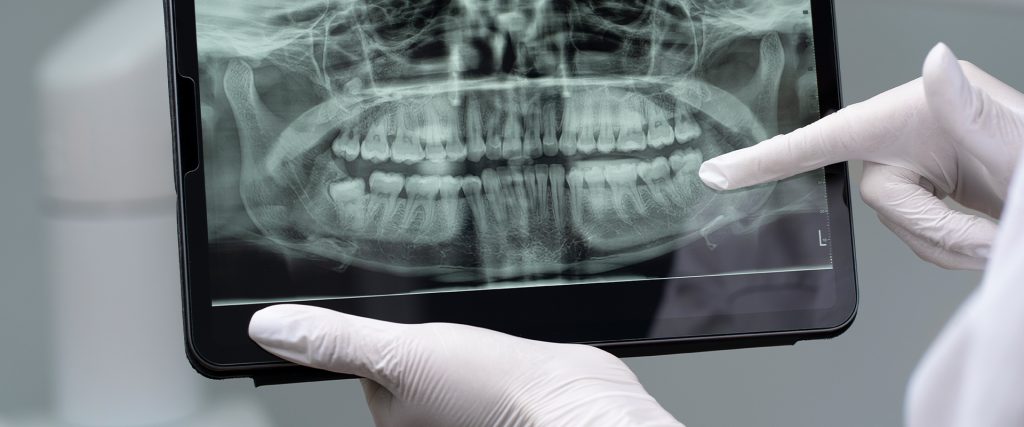

Hatay Dörtyol Temporomandibular Eklem Tedavisi süreci, hastanın şikayetlerinin dinlenmesi ve detaylı bir muayene ile başlar. Uzm. Dt. Erdal Yıldırım gibi bu alanda deneyimli bir hekim tarafından uygulanan klinik değerlendirmeler, çene hareket açıklığı, ağrı noktaları ve fonksiyon kaybı gibi durumları ortaya koyar.